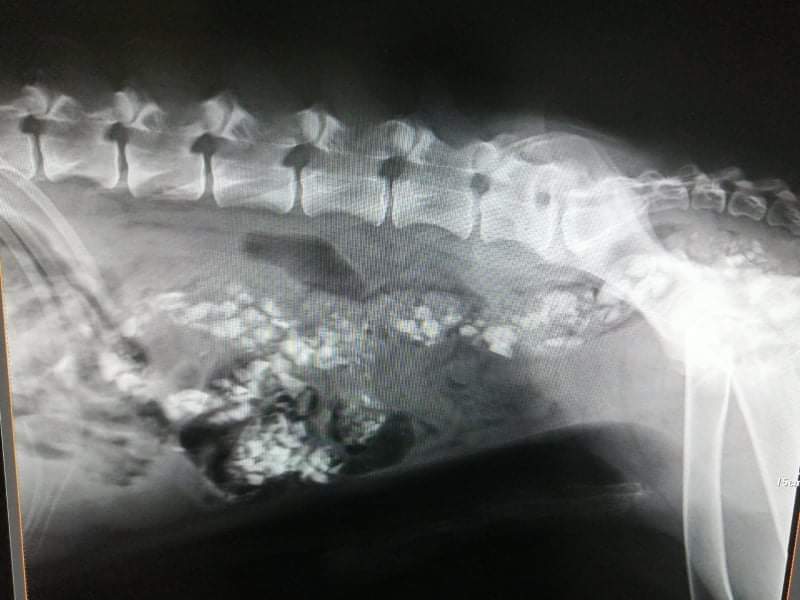

Desetogodišnji Car je tko zna koliko dugo životario kopajući po kantama za smeće da bi se prehranio, a nakon što su ga volonterke Udruge Sirius spasile i odvele u Slavoniju, RTG kod veterinara je pokazao da se pas prehranjivao i – kamenjem.

Car je sada dobro, kaže nam Petra Novinc. Pomak je očigledan, a s 28 kilograma koliko je imao kada su ga preuzeli, u kratko vrijeme ‘nabacio’ je pet kilograma. Isprva od iscrpljenosti, bolova i kamenja u trbuhu nije mogao jesti, no kako se stanje poboljšavalo, kaže Petra, Car s užitkom jede medicinske konzerve, a polako prelazi i na suhu hranu.